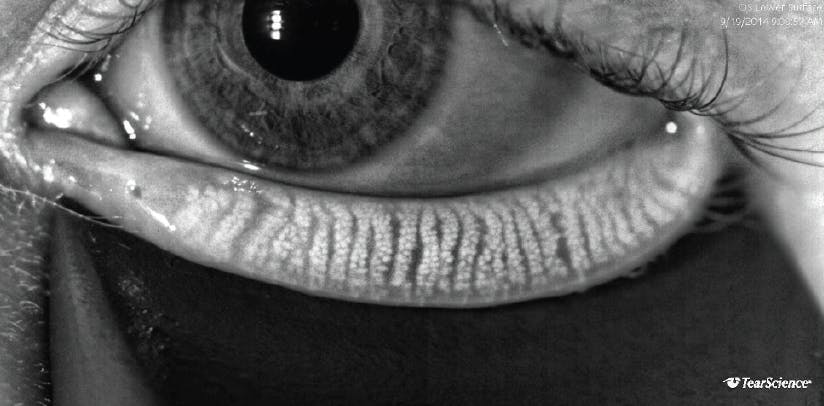

LipiScan noninvasively assesses meibomian gland structure; it uses dynamic illumination to minimize reflections and adaptive transillumination to provide equal lighting across the surface of the eyelids. Normal acini appear as discrete linear groups of light gray circular structures, whereas meibomian gland atrophy is seen as a darker gray absence of those structures. Serial images can be used to track the progress of therapy and improve patient compliance. Once meibomian glands atrophy, their function decreases, and their ability to regenerate is lost. Widespread destruction of glands seen on LipiScan images could therefore identify patients who may be less responsive to LipiFlow treatment (Figures 1–4).14

Figure 3. Adaptive transillumination with the LipiScan shows normal meibomian gland structure without dropout.